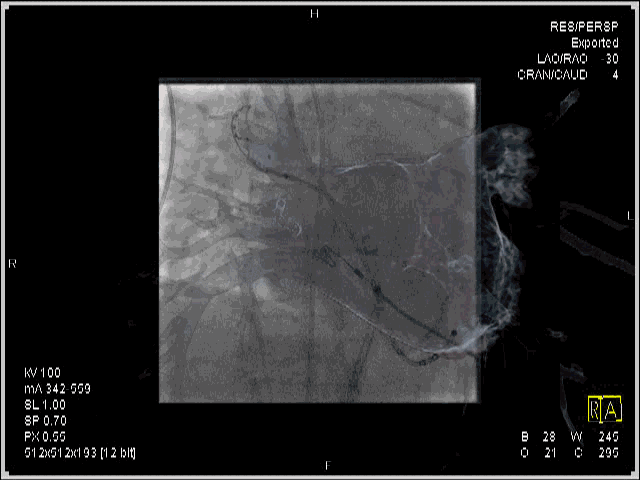

左上肺静脉造影及融合

影像融合下用于冷冻球囊的定位

右上肺静脉消融补点及起搏验证,可于X线直视下展示消融导管头端与CT影像的空间相关性

动态影像融合引导房颤冷冻消融治疗

牛国栋教授介绍到:在进行房颤冷冻球囊消融时,在X线造影下观察到的只是平面投影结构。由于肺静脉和心脏结构的复杂性,在进行导管操作时,往往会出现一些困难。结合影像融合技术,可以三维地呈现肺静脉分叉情况和心房结构,能指引导管操作、球囊定位,缩短进入肺静脉的时间即X线曝光时间,从而进一步降低射线量。随着这项技术的不断探索完善,我认为对于CRT植入术、左心耳封堵术、冷冻球囊消融术等有一定帮助。

本次手术中,患者右肺分支比较多,通过影像融合CT导入,帮助我们准确判断了肺静脉分支的位置。射线量暂未观察到明显变化。但是,由于CT建模在心房舒张期,术中心房处于收缩舒张交替状态,为了确保模型和真实心脏运动完全贴靠,还需要继续探索和努力。